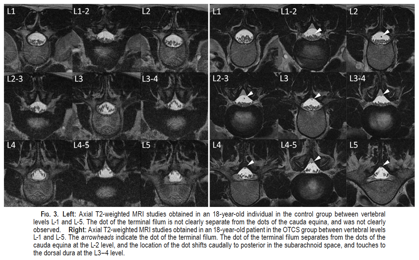

IMAGE AT THE TOP RIGHT. Axial images of lumbar Magnetic Resonance Imaging in the prone position to assess the position of the intradural filum terminale:

- On the left: images of a healthy person from the control group;

- On the right: images of a patient with occult tethered cord syndrome. In patients with occult tethered cord syndrome, the filum terminale does not move anteriorly with the nerve roots due to gravity but remains in a posterior position (WHITE ARROWHEAD).